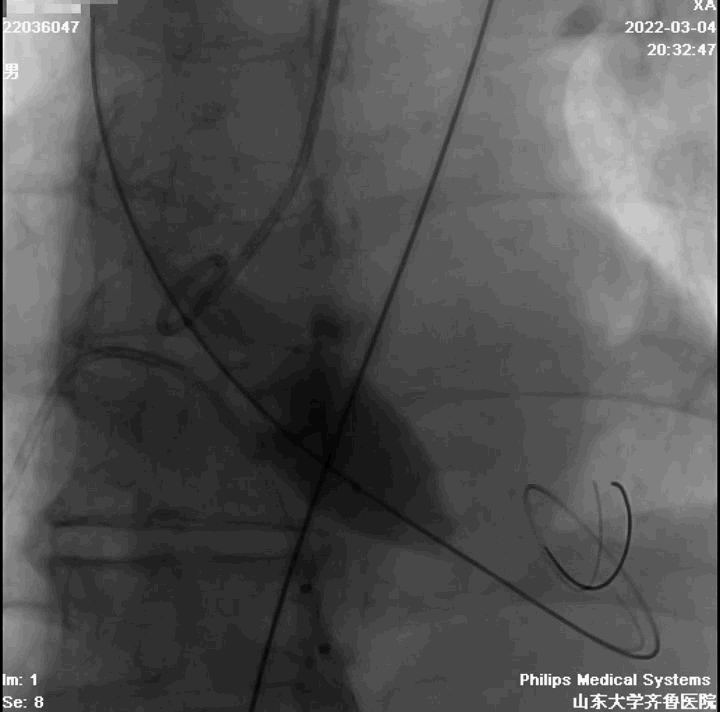

起始缓慢释放

造影观察

瓣膜工作,造影观察

完全释放

造影

球囊后扩

最终结果

术中评估球囊扩张效果,放弃已经预装载TAV30瓣膜,植入TAV27型号瓣膜,压差由81mmHg降至5mmHg,EF由38%升至61%。